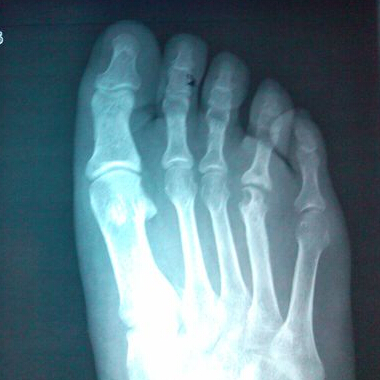

(图:治疗前鲁先生的x光图,可明显看出拇指关节肿大、外翻)

X线示:左足跖骨骨头处出现溶骨性缺损。